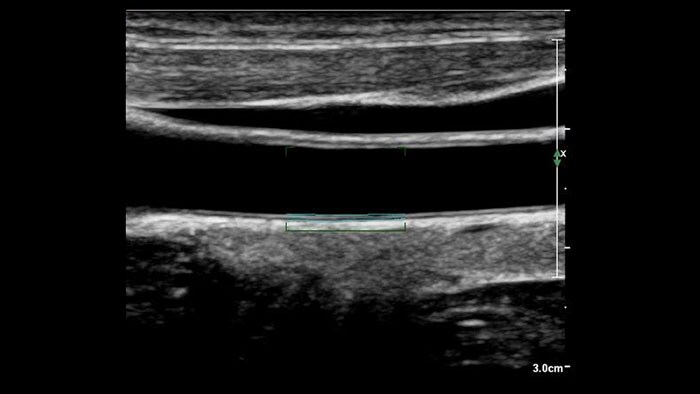

US Q-App Intima Media Thickness (IMT) provides easy and consistent measurement of intima media thickness in carotids and other superficial vessels. Report IMT values and append them to patient reports.

US Q-App Vascular Plaque Quantification (VPQ) helps you perform comprehensive volume analysis for carotid plaque; a significant indictor in cardiovascular disease. Automatically measure plaque composition throughout a captured volume, percent area vessel reduction and other characteristics using 3D technology. Results may be posted to patient exams.